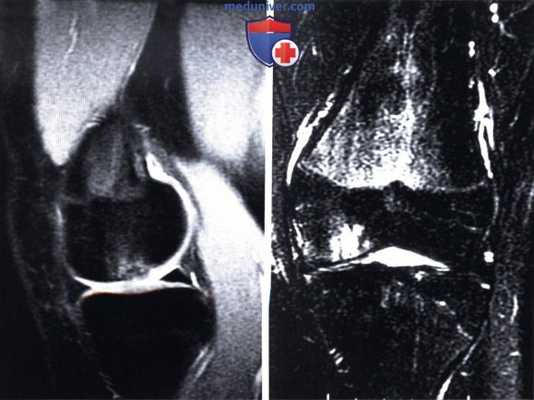

3) Магнитно-резонансная томография (МРТ):

1. Целостность мениска и состояние его периферической зоны (рис. 1 и 2):

• Остатки нативного мениска можно использовать в качестве шаблона для определения размеров необходимого трансплантата мениска

2. Оценка состояния суставного хряща, признаки отека субхондральной кости, прилежащих участков костного мозга или остеонекроза

3. Признаки повреждения крестообразных или коллатеральных связок коленного сустава

Длительность хирургического вмешательства обычно зависит от степени повреждения мениска. В среднем артроскопия длится 60 минут. В сложных случаях она может продолжаться 1,5-2 часа. На МРТ справа — разрыв заднего рога мениска, слева — здоровый мениск.